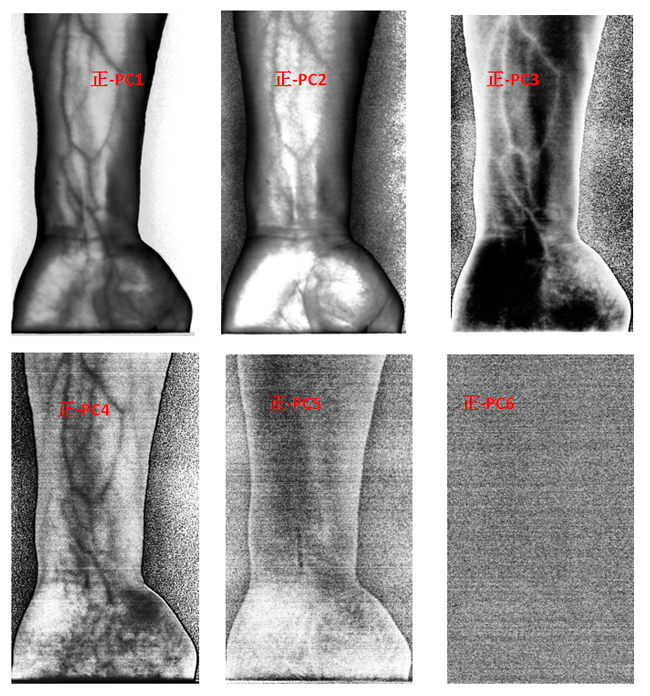

为了客观地识别手臂上的静脉,对经预处理后的高光谱数据进行主成分分析(Principal Component Analysis, PCA),去除波段之间的多余信息、将多波段的图像信息压缩到比原波段更有效的少数几个转换波段下。图9为手臂正反面经PCA变换后的前6个主成分。

图9 手臂正反两面PCA处理后的前6个主成分